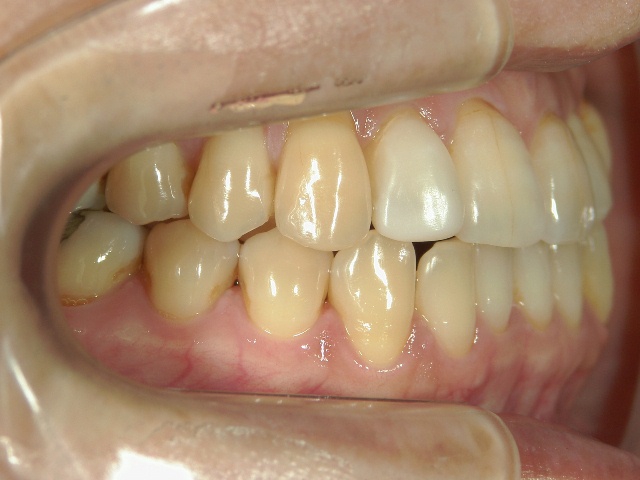

矯正歯科 治療前 右